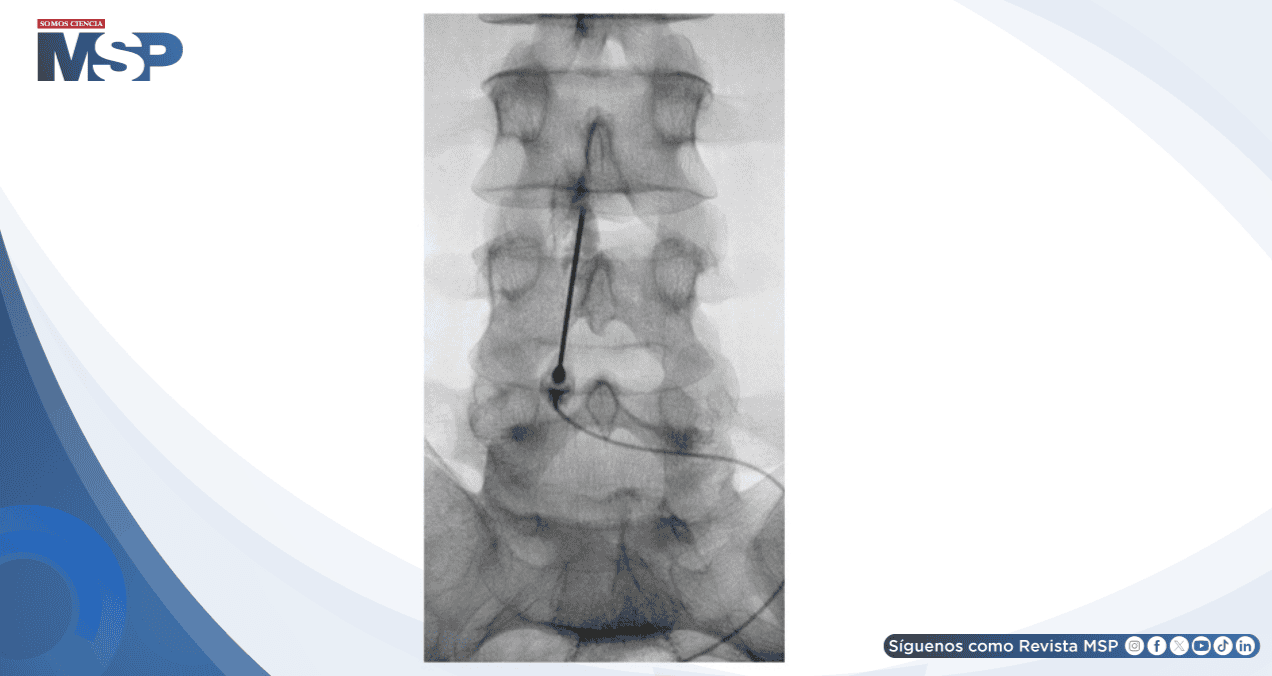

Bajo guía fluoroscópica, se accedió al espacio epidural L3-L4 utilizando aguja de Tuohy calibre 18 mediante técnica de pérdida de resistencia.

Se confirmó la colocación epidural con inyección de contraste fluoroscópico y se administró una inyección lenta de 20 mL de sangre autóloga. El procedimiento transcurrió sin complicaciones y en menos de una hora el paciente experimentó resolución completa de los síntomas.